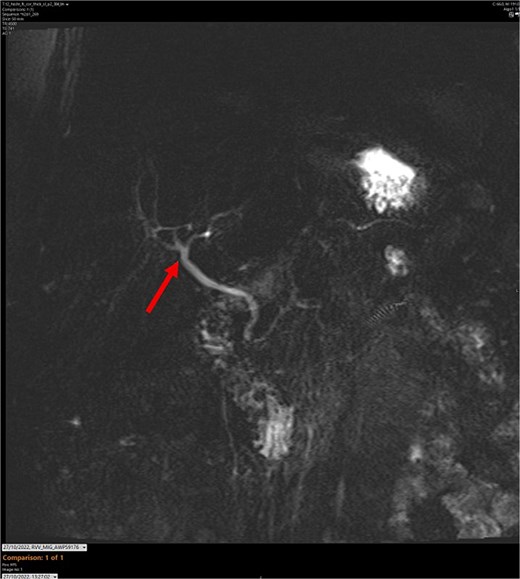

On admission, the patient’s blood tests showed normal inflammatory markers, liver function markers, and amylase (Table 1). The patient underwent an abdominal ultrasound scan, which did not visualize gallstones or the gallbladder. A computerised tomography (CT) abdomen-pelvis scan was done, and the gallbladder could not be visualized (Figs 1 and 2). Further investigations, which include a magnetic resonance cholangiopancreatography (MRCP) and hepatobiliary iminodiacetic acid (HIDA) scan, confirmed a gallbladder bud with an intact biliary tree (Figs 3–6). The patient denied a history of a cholecystectomy. She was diagnosed with gallbladder agenesis.

MR maximum intensity projection scan. The arrow points to the largely intact biliary tree. The cystic duct cannot be seen branching from the common bile duct.